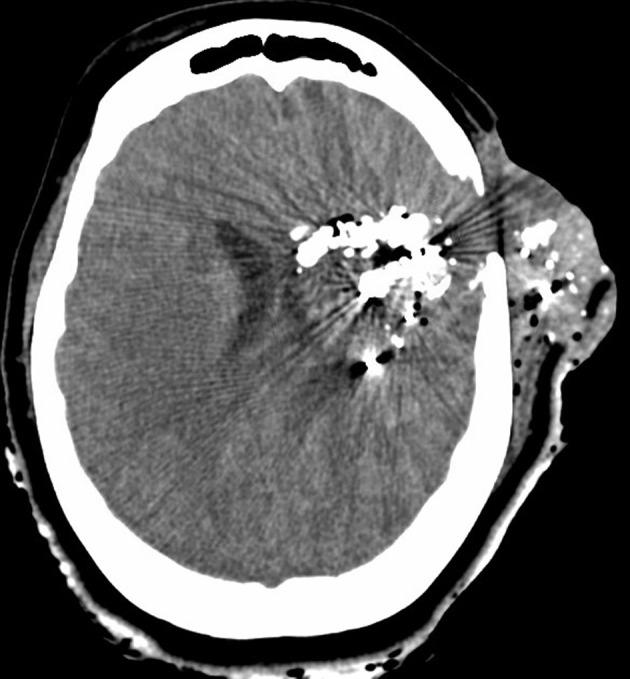

A 24-year-old female with history of traumatic brain injury with associated skull fractures due to a gunshot wound to the head 6 months prior presented to the ED in hemorrhagic shock secondary to epistaxis. After stabilization with the administration of blood products, Computed Tomography with Angiography (CTA) imaging of the head and neck was obtained and revealed a 3.1 × 2.2 × 2.5 cm pseudoaneurysm of the cavernous portion of the right internal carotid artery penetrating through the base of the skull into the ethmoidal sinus. The patient was taken for formal angiography by interventional radiology-and a partially thrombosed daughter sac of the initial aneurysm was identified and believed to be the source of the hemorrhage. The aneurysm was successfully coiled and occluded using ONYX embolization. Postoperatively, the patient returned to her baseline mental status without any acute complaints. The patient was discharged back to her nursing home 2 days later with a 3-week follow-up CTA revealing persistent occlusion of the aneurysm and a patent internal carotid artery.

一名24岁女性,6个月前因头部枪伤导致创伤性脑损伤并伴有颅骨骨折,因鼻出血继发失血性休克被送往急诊科。在输注血液制品使其病情稳定后,对头颈部进行了计算机断层血管造影(CTA)成像检查,结果显示右侧颈内动脉海绵窦段有一个3.1×2.2×2.5厘米的假性动脉瘤,该动脉瘤穿过颅底进入筛窦。患者被介入放射科送去进行正式血管造影,发现了最初动脉瘤的一个部分血栓形成的子囊,并认为这是出血源。使用Onyx栓塞剂成功地对动脉瘤进行了弹簧圈栓塞和封堵。术后,患者恢复到基线精神状态,无任何急性不适主诉。患者于两天后出院回到养老院,3周后的CTA随访显示动脉瘤持续闭塞,颈内动脉通畅。